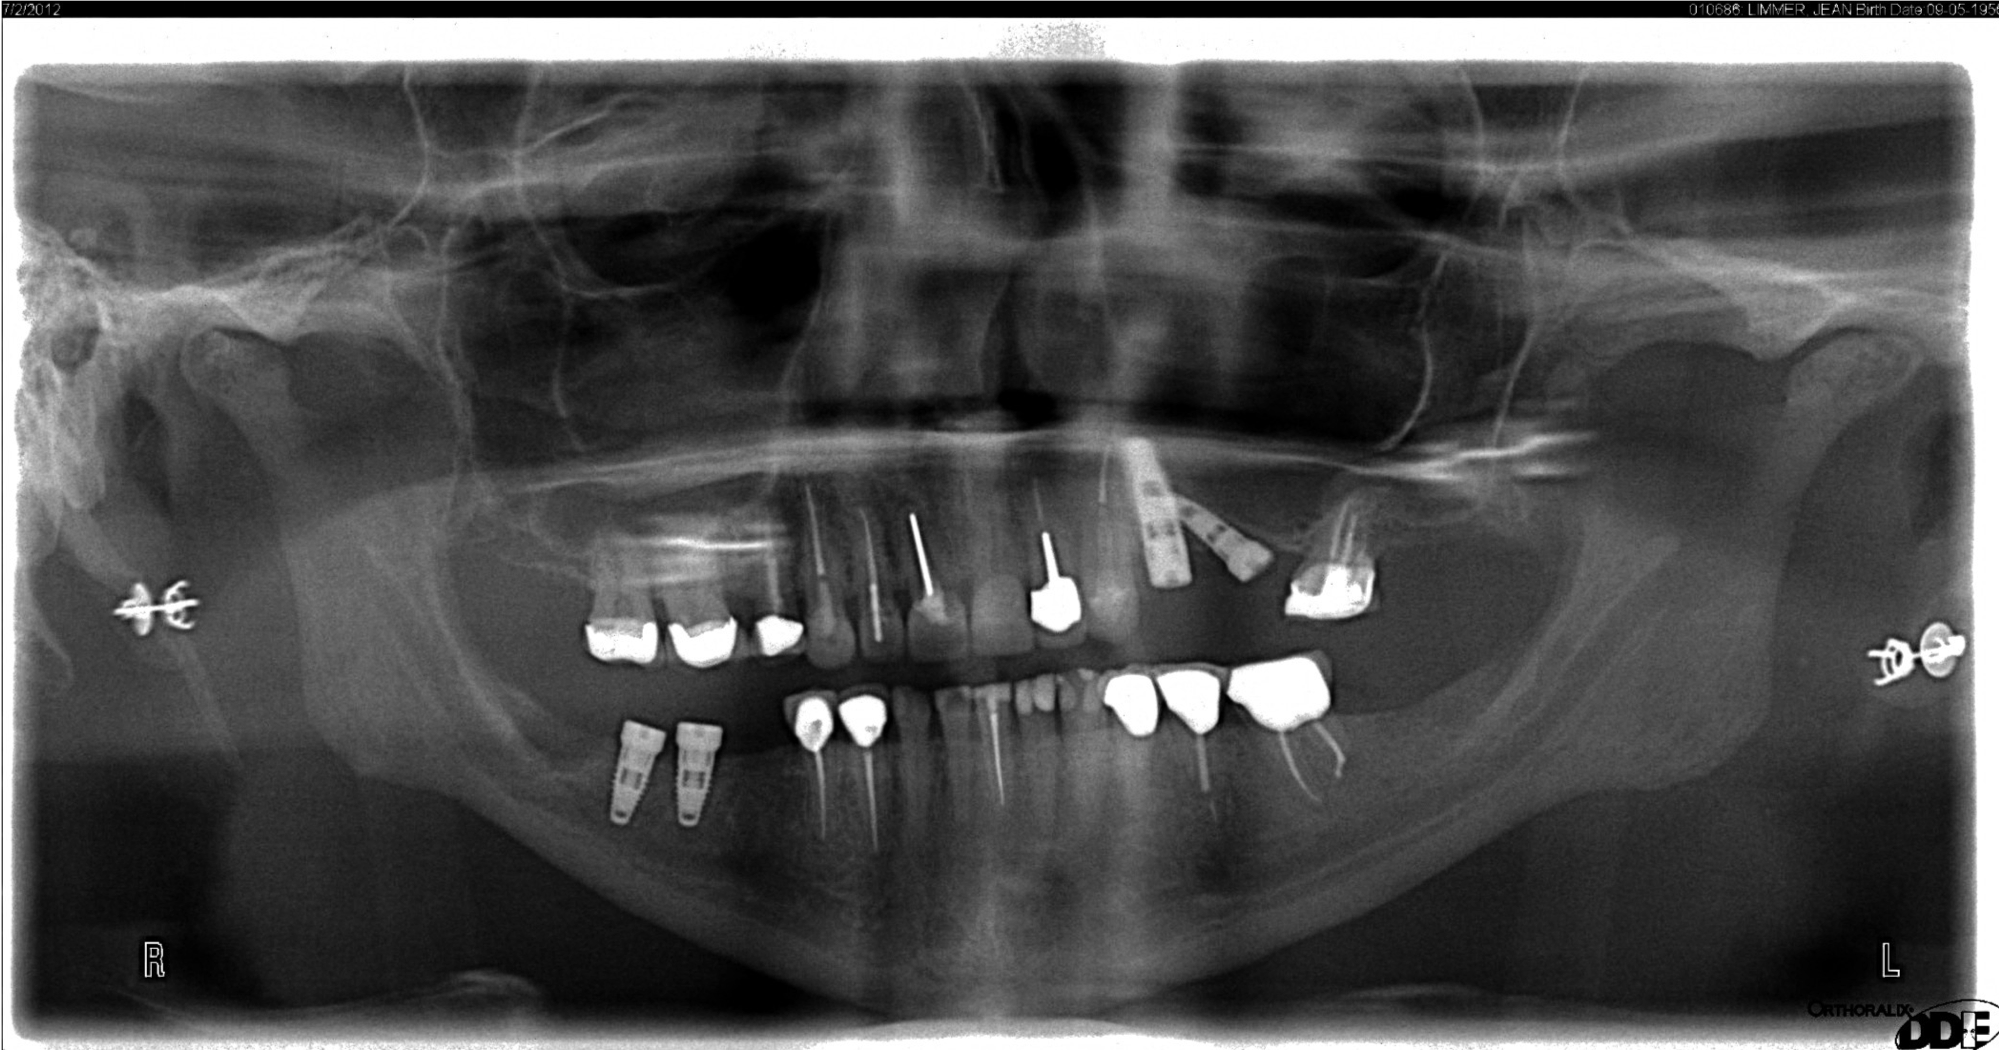

The panoramic radiograph is a good diagnostic tool to implement as well, but with rotation of the cone around the patient's head and neck, there is going to be a distorted bone level. Figure 7 shows an artifact that can occur with the panoramic radiograph, where the patient's earrings relay across the ridge. Artifacts such as this and other distorted findings indicate that the radiograph should not be the sole tool for implant placement.

Fig 7. A panoramic radiograph is an effective diagnostic tool; however, distortions occur, and artifacts may appear.

Figure 7